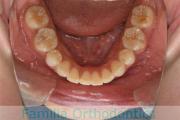

- ≫治療前

上顎

下顎

- ≫治療後